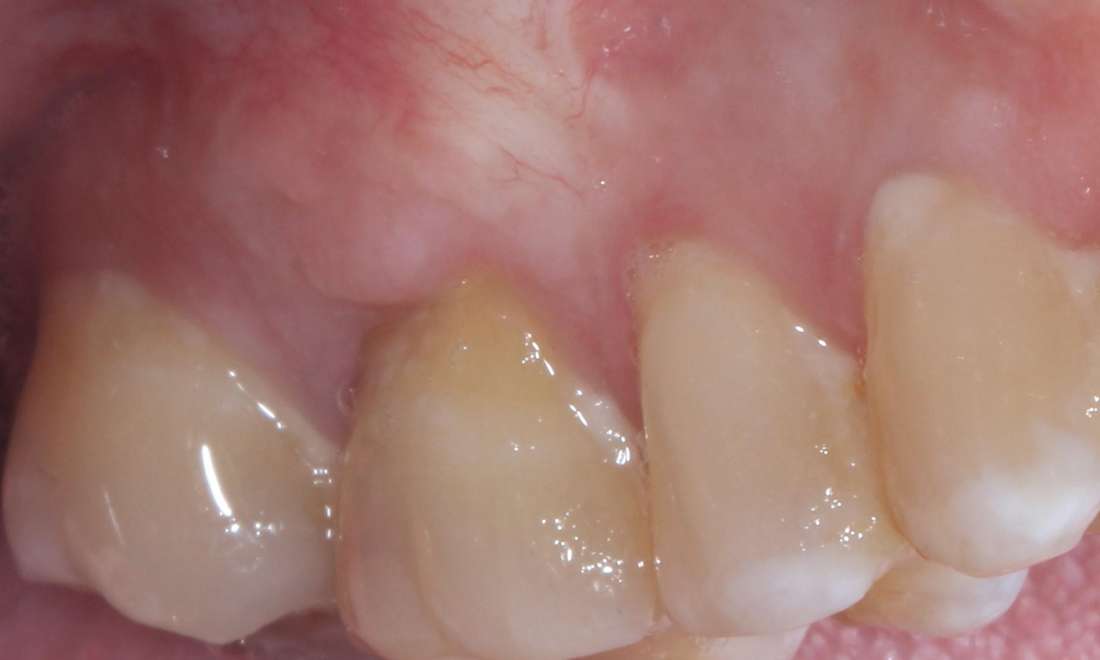

Before: Patient reports gums receding causing a plaque trap

Before